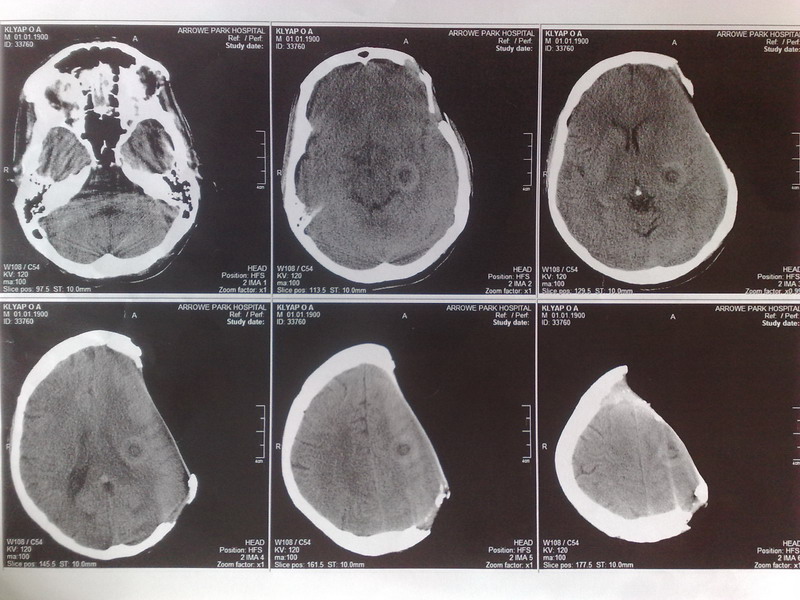

За последний год дефект немного увеличился. Несколько дней назад было сделано КТ на котором

поражения головного мозга не обнаружено. Додаю результаты КТ.